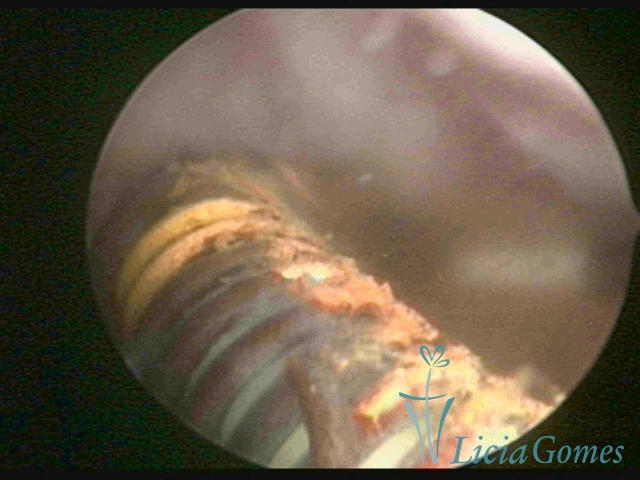

Cavidade uterina com resíduo de DIU, fragmentado, colocado há 46 anos